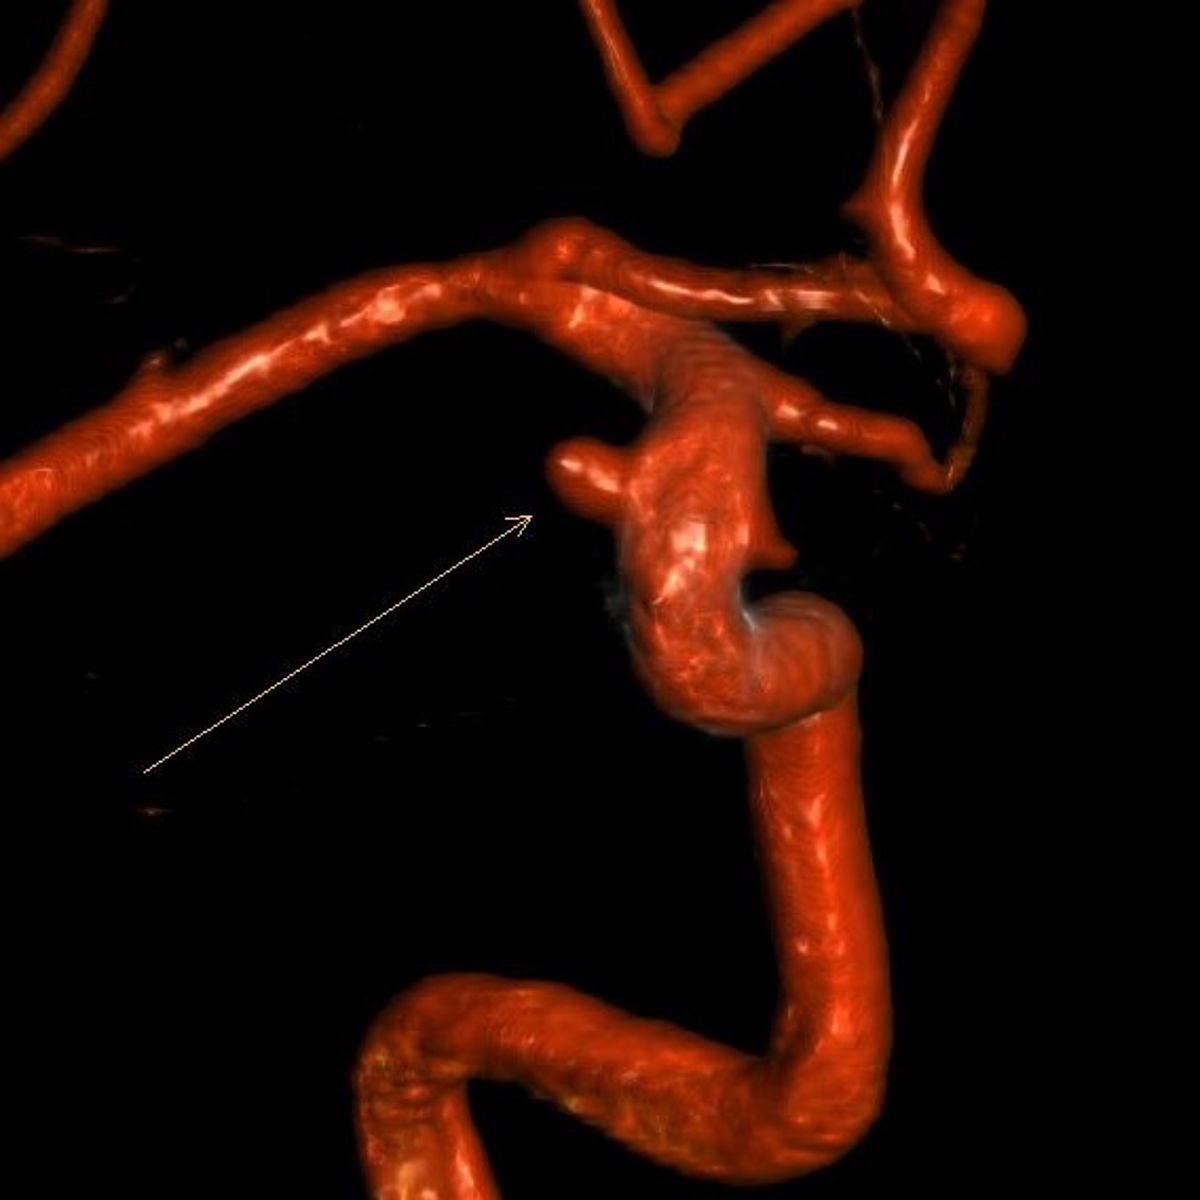

Aneurysmen sind Aussackungen der Gefäßwand, die vor Allem an den Hirnschlagadern durchaus häufig sind - etwa 5% der erwachsenen Bevölkerung tragen ein oder mehrere Aneurysmen in ihrem Kopf.

Die Hauptgefahr geht von einem Riss eines solchen Aneurysmas aus, was zu einer lebensgefährlichen Blutung in die Gehirnhäute oder das Gehirn führen kann (Subarachnoidealblutung).